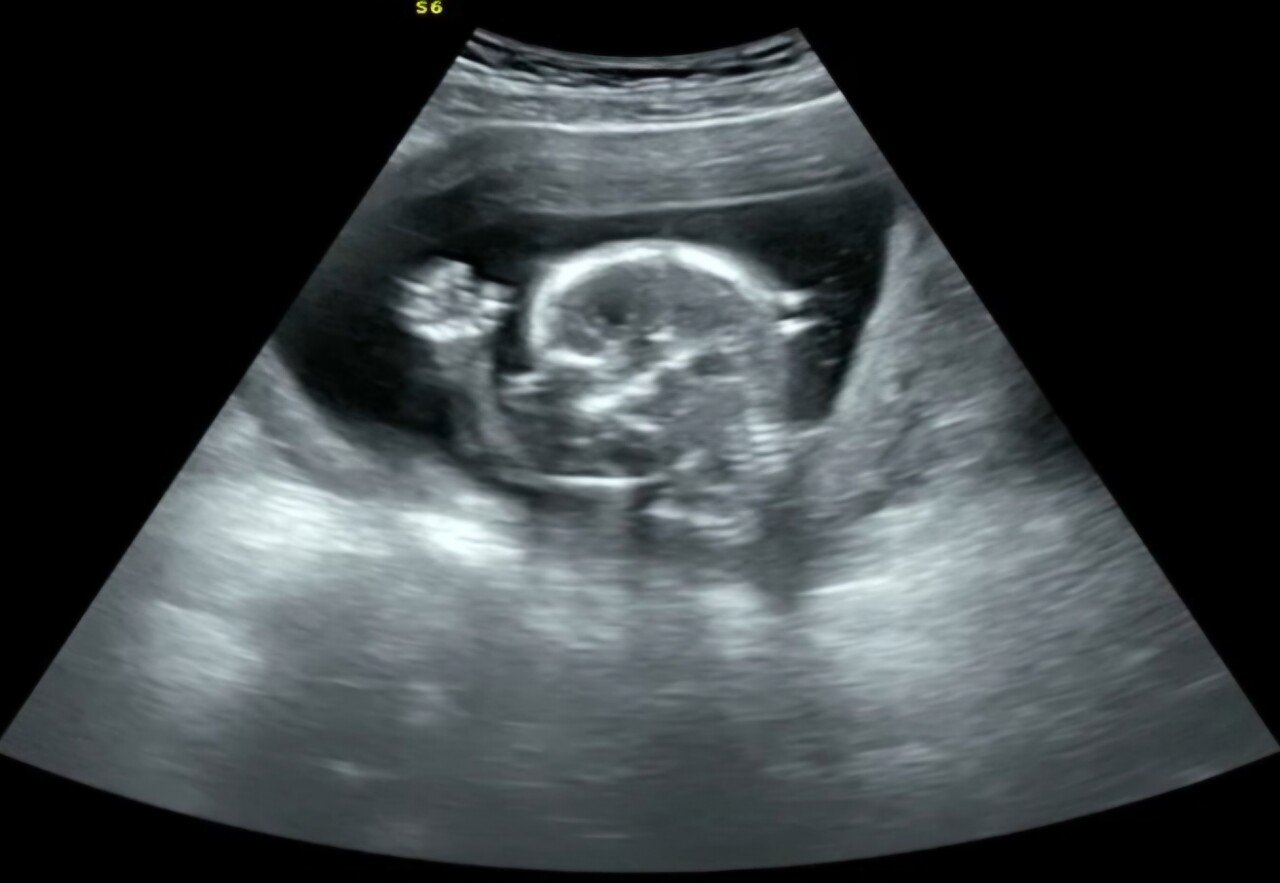

21주된 남자아이의 예비 아빠가 합법적으로 포좀 빨고 싶습니다.

오늘 육안으로 성별확인 했네요